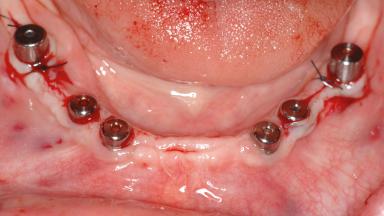

Le Fort I Interpositional Graft and Mandibular Sandwich Osteotomy for Maxillofacial Rehabilitation after Severe Periodontitis

A 47-year-old woman who had suffered from aggressive periodontitis requiring a number of periodontal interventions over more than 10 years was referred by her general dental practitioner and periodontologist for bone augmentation and implant therapy. Her failing dentition had already been scheduled for extraction. The patient expressed a desire for implant-supported fixed restorations and esthetic improvement of her lower face. She had agreed to consult with a maxillofacial surgeon after the referring dentist had suggested bone augmentation. An initial examination by the maxillofacial surgeon revealed mobility of all residual teeth in a patient who was very unhappy with the function of her removable partial dentures. Due to periodontally migrated flaring teeth and loss of occlusal support, the vertical dimension of occlusion was dramatically reduced. The patient was displeased with her lower face because of deepened nasolabial, commissural, and supramental folds.

# of Implants 14

Type of Implants Two-Piece

Bone Augmentation Horizontal|Sinus Floor Elevation|Staged|Vertical

Augmentation Materials Autogenous chips|Autogenous block(s)|Xenogenous|Membrane

Defining Characteristics Fully edentulous upper jaw to be rehabilitated with four or more implants

Modality Fixed hybrid bridge on 5+ implants